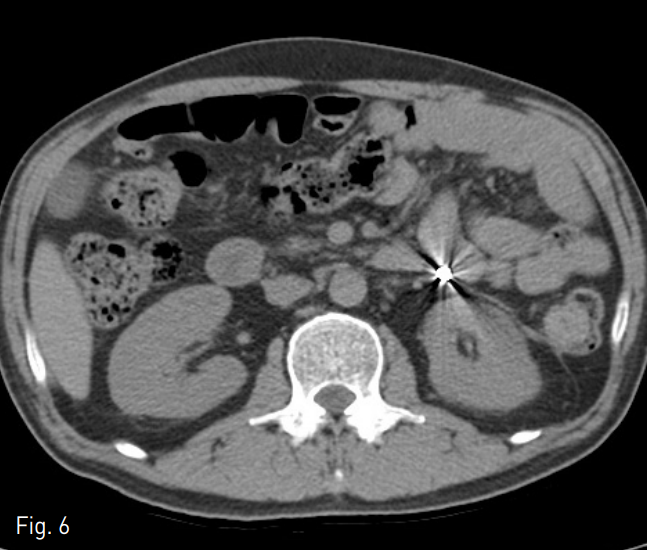

마지막 시술 3주 뒤 외래에서 시행한 경과 관찰 비조영 전산화 단층촬영에서 이전에 보이던 췌장주위구역과 전방콩팥주위공간에 구획화된 액체 저류나 오른 결장주위 공간의 액체 저류는 보이지 않음. 이전 색전술이 시행된 소장의 주위로도 누출을 시사하는 비정상 액체 저류는 보이지 않았음 (Fig. 6).

Fig. 6

Contrast-enhanced axial CT scan on 2 months after tract embolization shows nearly disappeared state of previously demonstrated walled-off necrosis and fluid collection at anterior perirenal space. There is no evidence of recurrence of jejunal fistula, too.